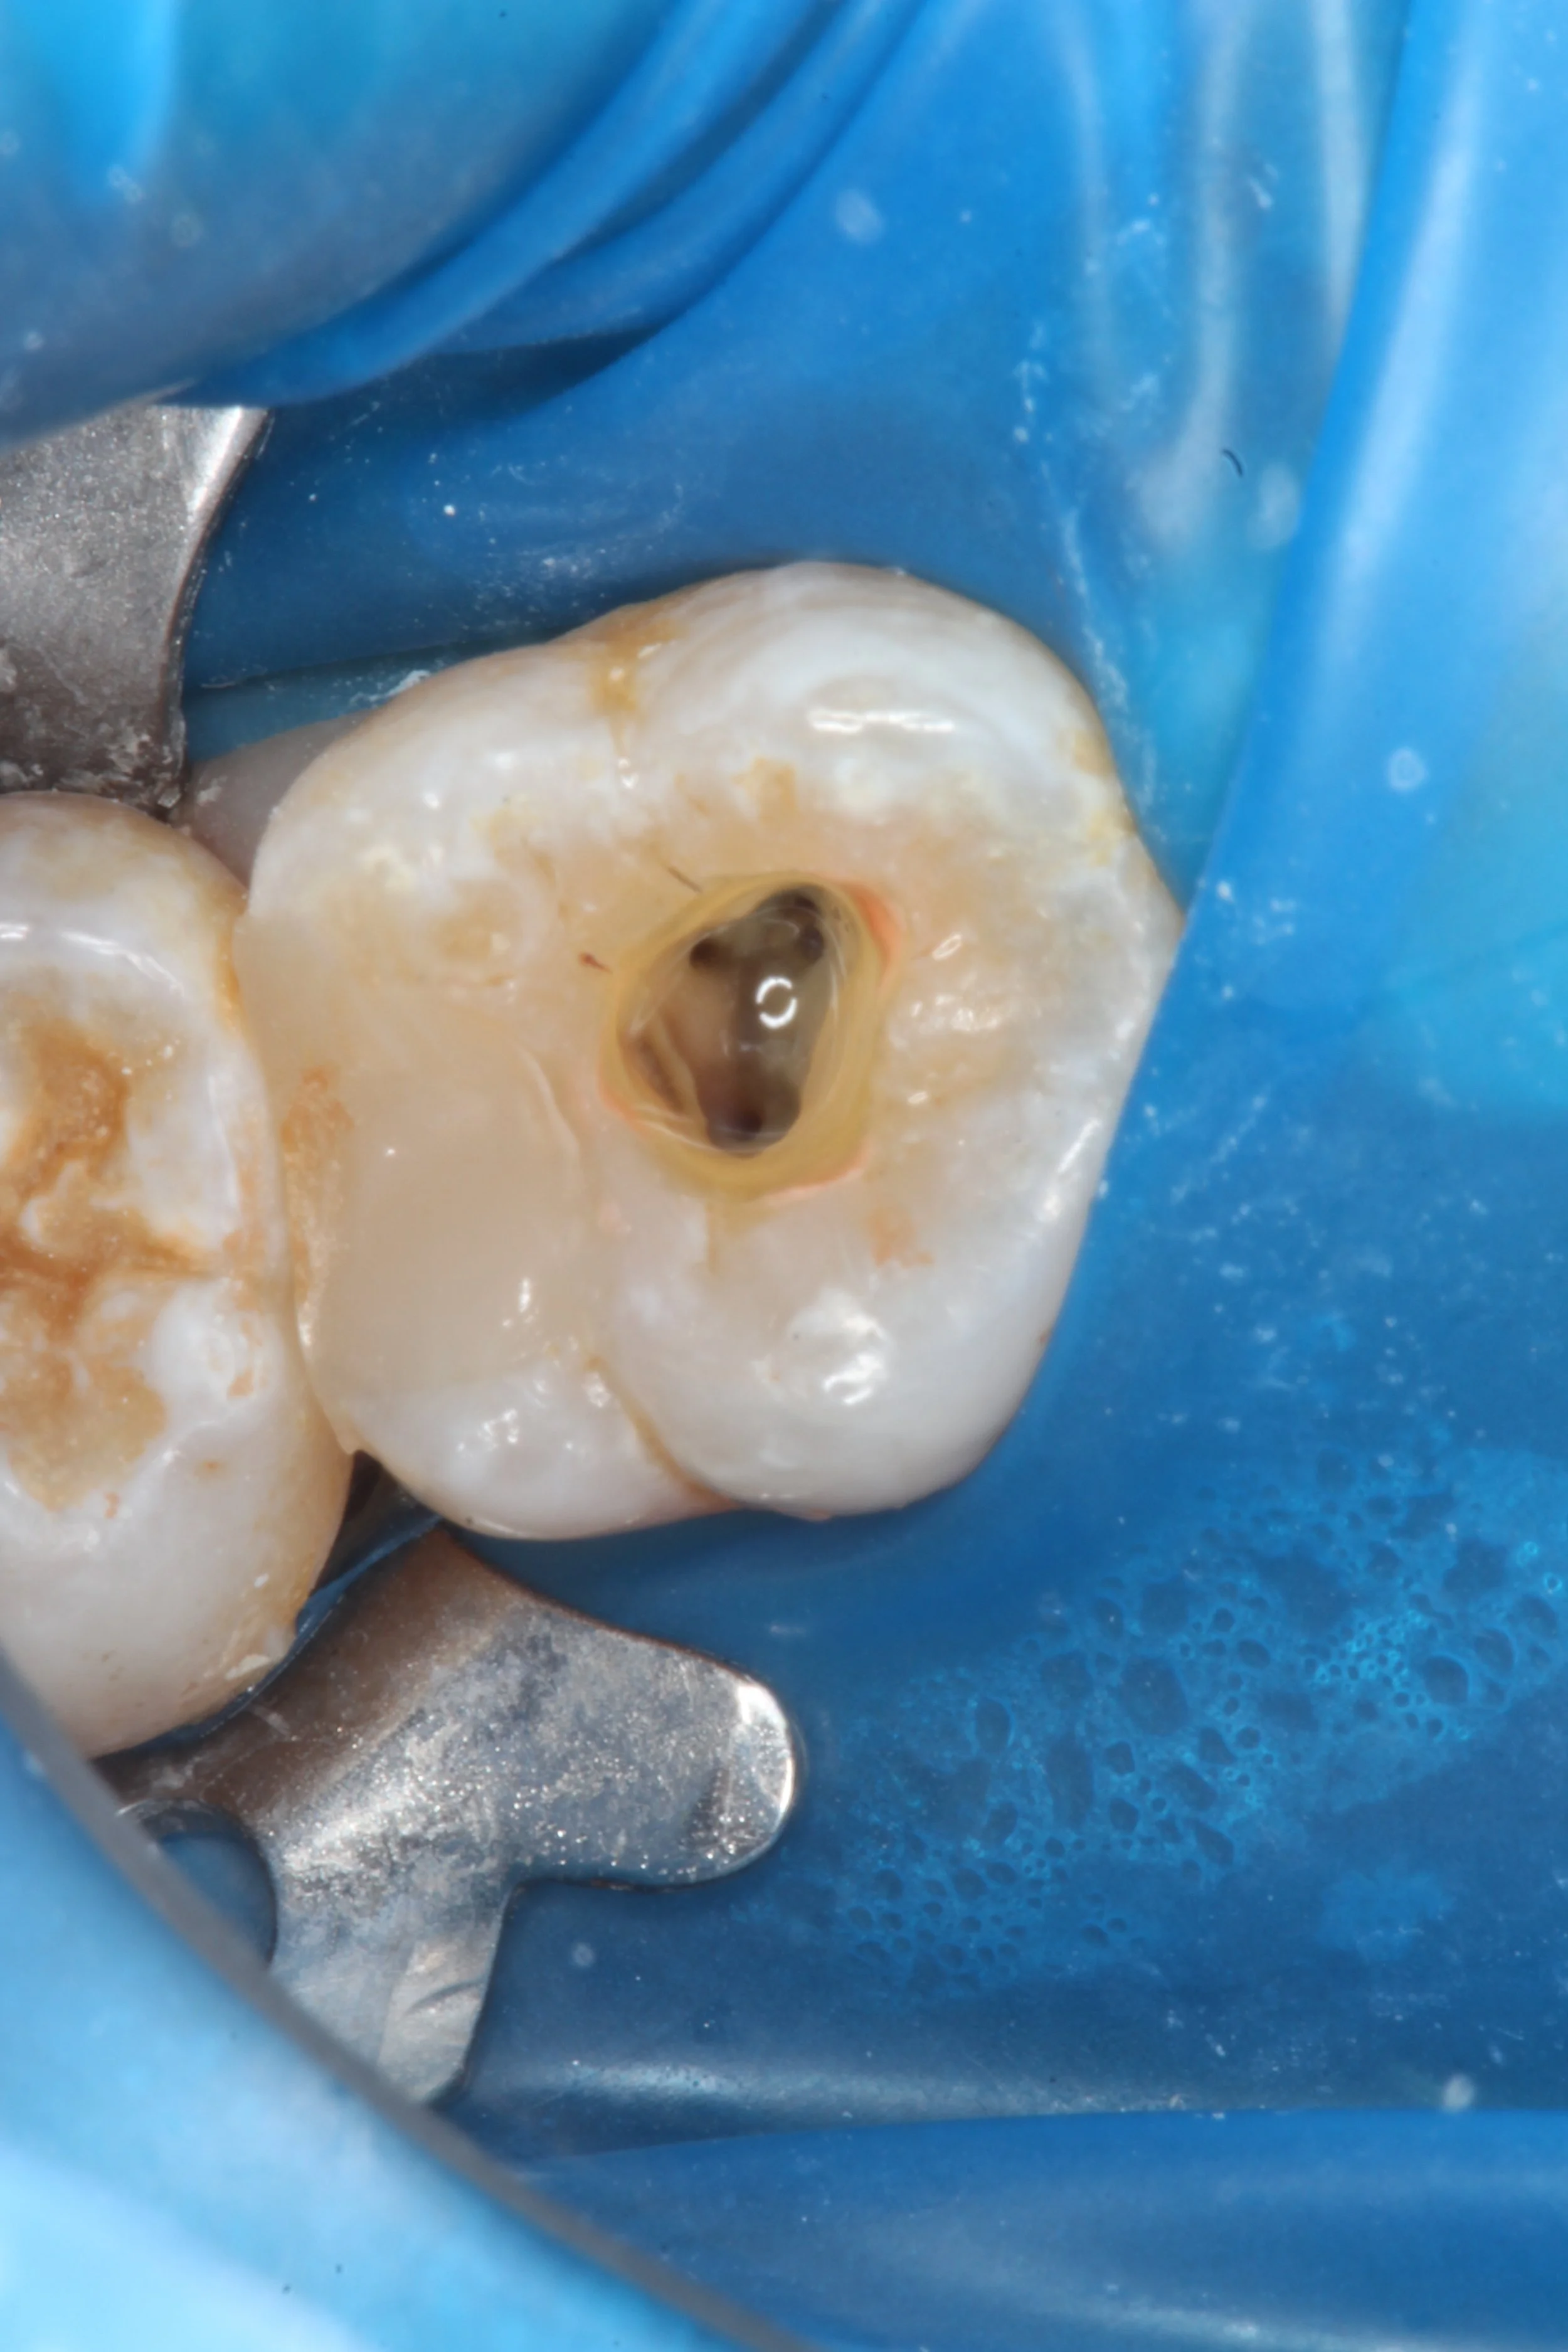

Position of MB2 orifice in the more traditional position. About 3-4mm palatal to MB2 orifice.